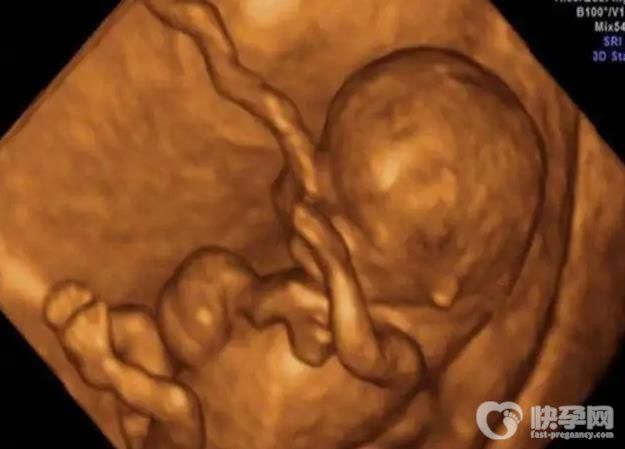

最明显的女宝b超图,一分钟学会B超怎么分析出男女!胎儿性别的话题一直是准妈妈们讨论的热点。在网上,一些珍贵的妈妈们分享了很长时间的经验,比如怀孕的症状和其他看待男女的方式,包括分享一些关于成功生女孩的怀孕期间的症状和反应。但其实光是这些是不允许的。准确率最高的是b超。如果b超位置好,仪器先进,胎月合适,可以通过b超看出宝宝的性别。通常b超单上的三条线、凸点、英文字母是最明显的特征。

一般来说,在医学上可以通过b超进行胎儿的性别鉴定,这是所有预测男女的方法中比较科学的方法。通常在胎儿16-20周(4-5个月)左右,可以清晰地看到女宝宝的生殖器官,肉眼完全可以分辨出来。还可以在b超上看看胎儿两腿之间的性别特征。这个b超是从屁股下面取的,清晰度取决于仪器。

1.三条线

b超图可以看到努宝的生殖器结构,上面有一条类似于线的横条。这是努宝胎儿的外生殖器结构,也就是我们所说的大***和大***。b超看的时候有时候是一条线,大部分时候是三条线。有了这个,努宝就可以更好的确认了。过了孕龄,此时,性别特征不仅明显,而且非常清晰,容易分辨。看到男女基本上十有八九;